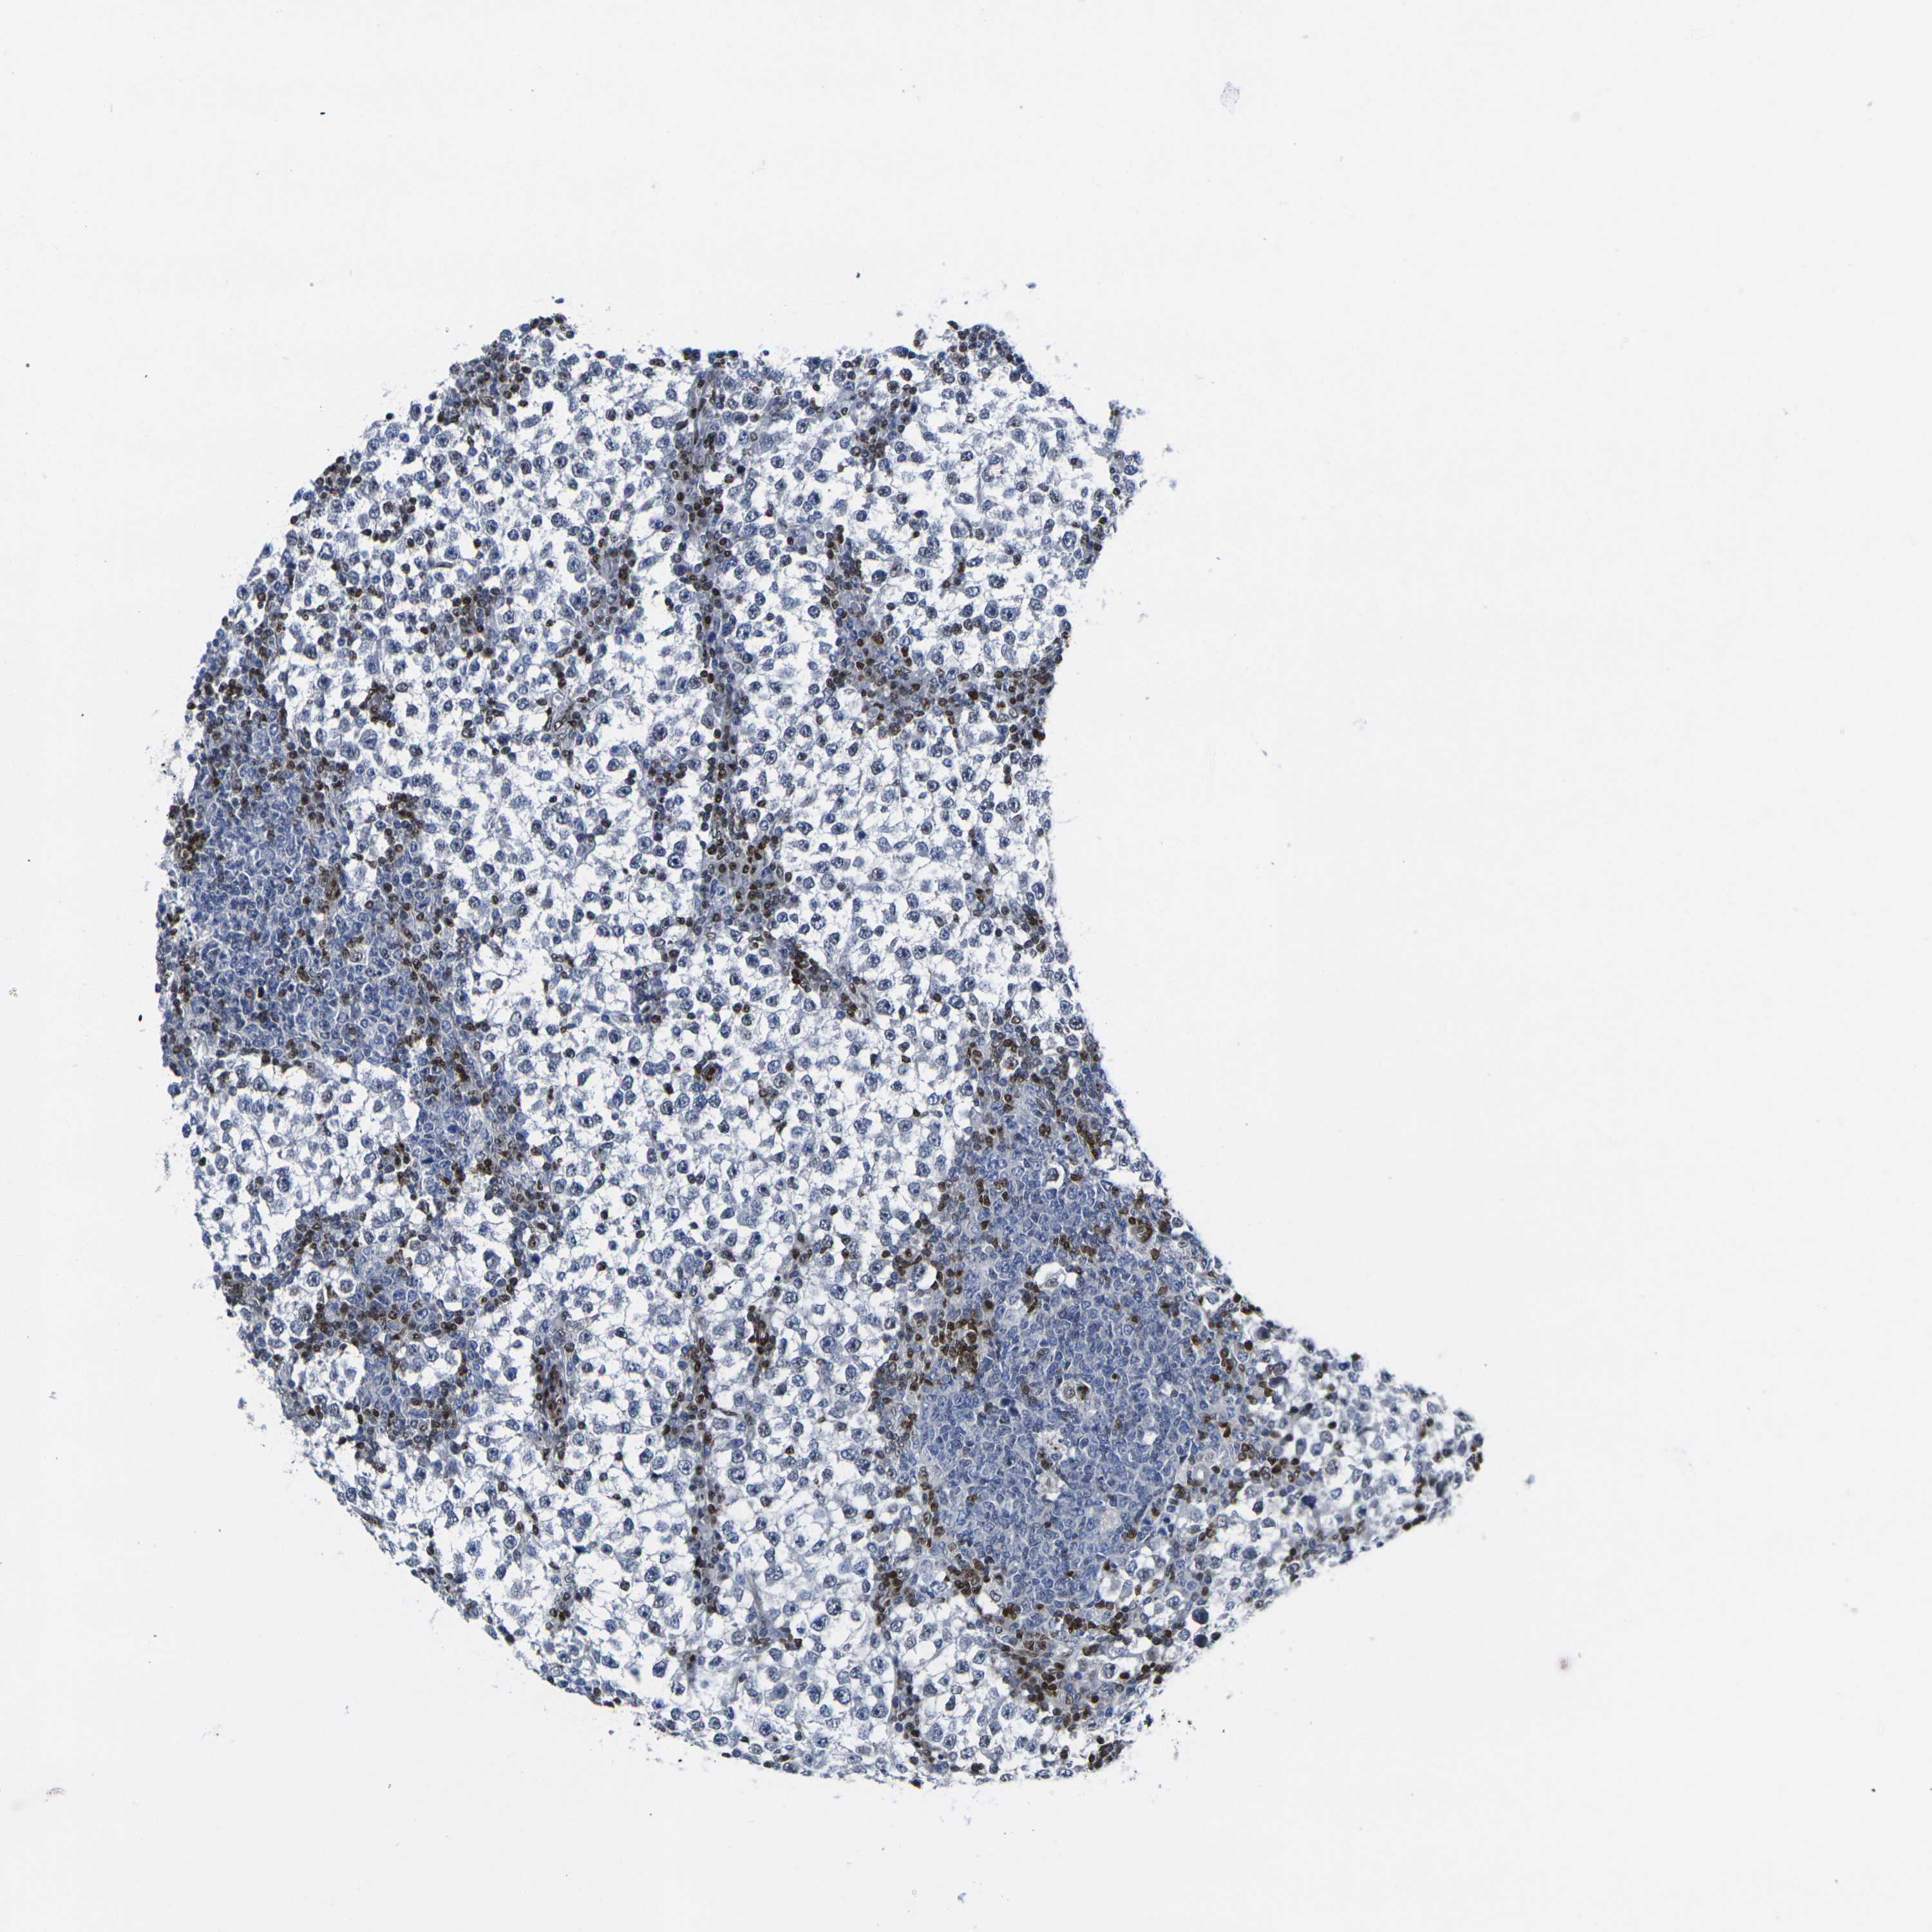

TESTIS CANCER - Protein expressioni

A mouse-over function shows sample information and annotation data. Click on an image to view it in a full screen mode. Samples can be filtered based on level of antibody staining by selecting one or several of the following categories: high, medium, low and not detected. The assay and annotation is described here.

Note that samples used for immunohistochemistry by the Human Protein Atlas do not correspond to samples in the TCGA dataset.

Antibody stainingi

Antibody staining in the annotated cell types in the current human tissue is reported as not detected, low, medium, or high, based on conventional immunohistochemistry profiling in selected tissues. This score is based on the combination of the staining intensity and fraction of stained cells.

Each image is clickable and will lead to virtual microscopy that enables deeper exploration of all samples and also displays staining intensity scores, fraction scores and subcellular localization as well as patient and tissue information for each sample.

Antibody HPA068431

Antibody CAB012235

Seminoma, NOS

Carcinoma, Embryonal, NOS